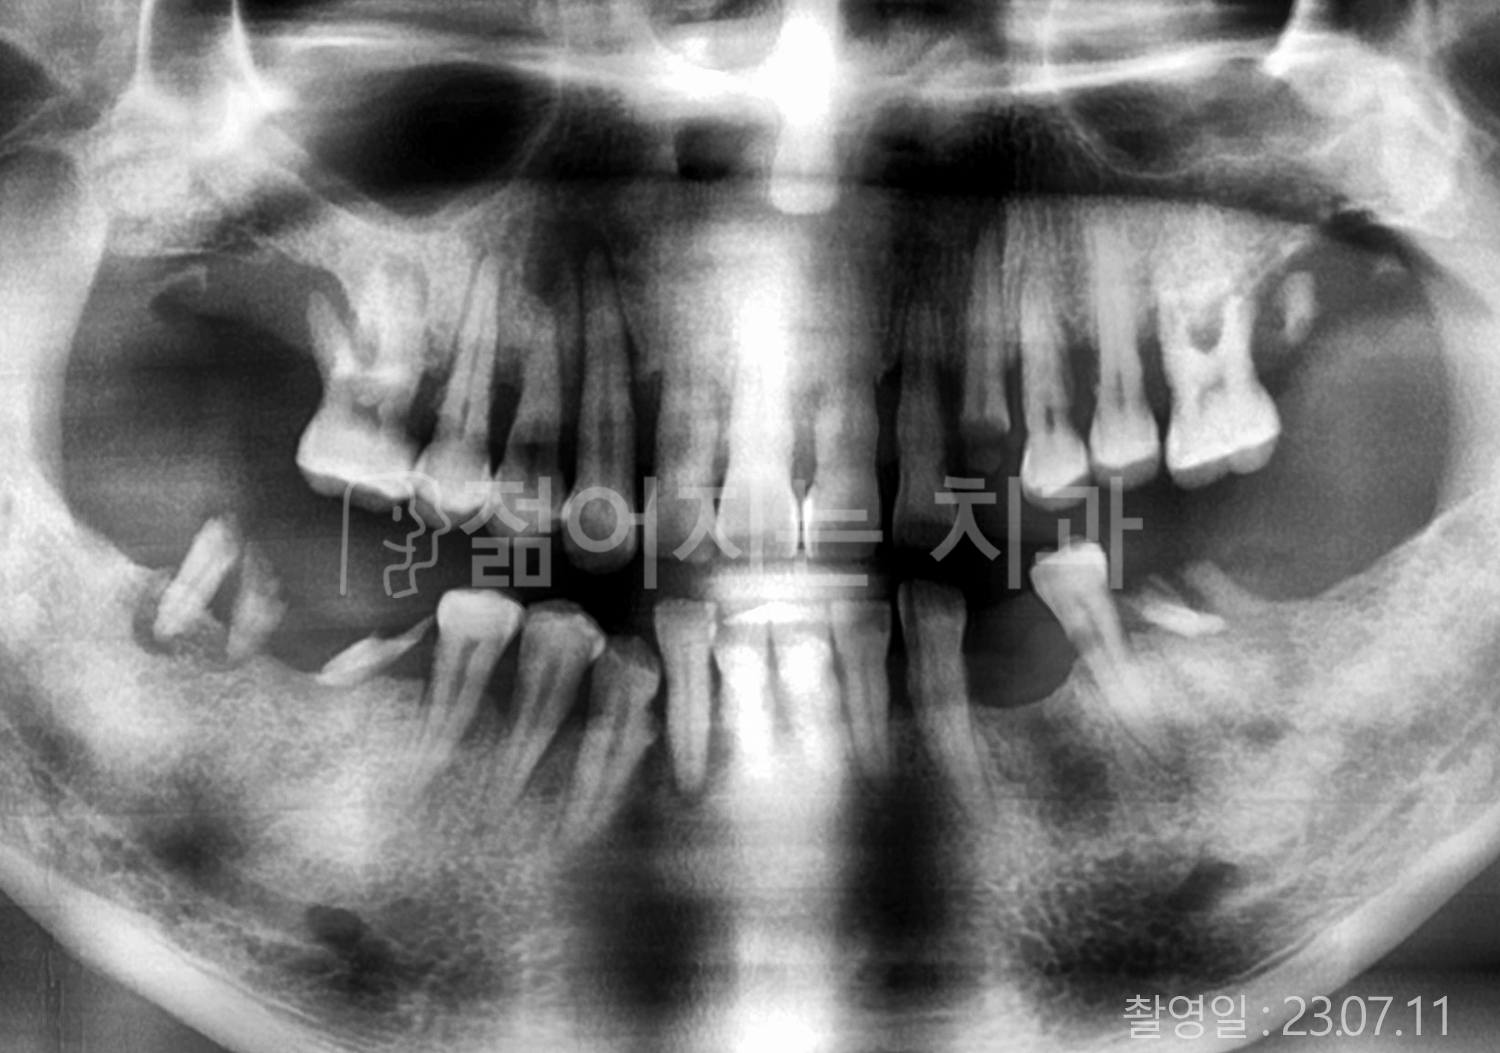

• 70대 고혈압, 당뇨 전체치아 10개 이상 임플란트

• 50대 고혈압, 당뇨 전체치아 10개 이상 임플란트

• 60대 고혈압, 당뇨 전체치아 10개 이상 임플란트

• 50대 전체치아 10개 이상 임플란트

• 70대 당뇨 전체치아 10개 이상 임플란트

• 80대 전체치아 10개 이상 임플란트

• 40대 전체치아 10개 이상 임플란트

• 60대 고협압, 고지혈증 전체치아 10개 이상 임플란트

• 60대 전체치아 10개 이상 임플란트